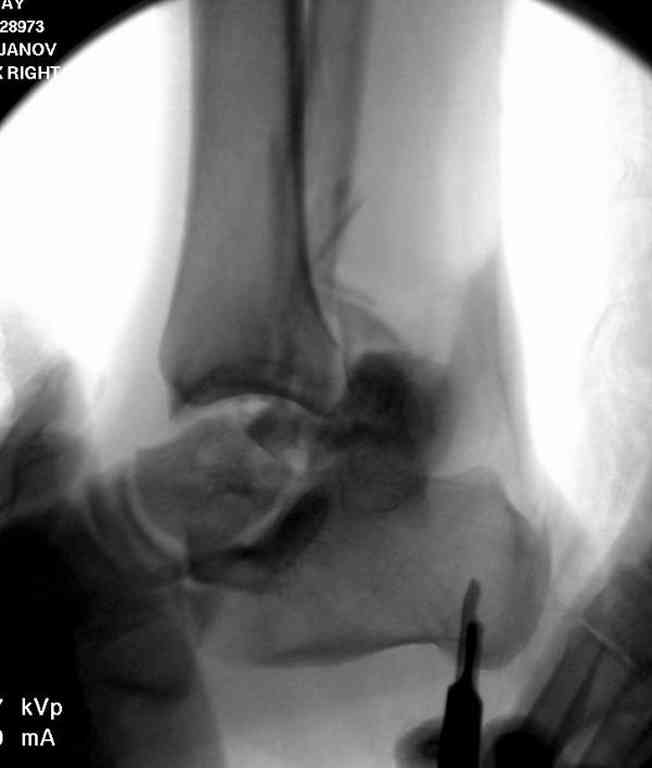

10 дней назад поступил с открытым повреждением медиальной лодыжки и переломо вывихом таранной кости. Ургентно сделана репозиция с наложением наружного фиксатора + Irrigation&Debridment.

Во время репозиции выявили повреждение заднего сухожилия м. тибиалис и задней большеберцовой артерии. Медиальную рану удалось закрыть частично и установлен вакуум.

Дважды провели Irrigation&Debridment с заменой вакуума.

Вчера провели фиксацию.